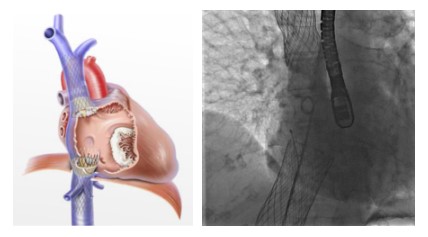

Il sistema utilizzato (TricValve) prevede l’impianto di due protesi biologiche a livello delle vene cave (superiore e inferiore) per prevenire il reflusso di sangue e trattare la congestione venosa.

Le protesi vengono impiantate attraverso un catetere inserito nella vena femorale, evitando così un’operazione a cuore aperto.